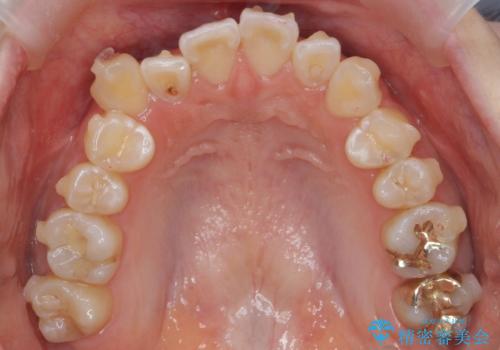

下の前歯の周りの骨は薄いことが多く、無理に並べると唇側の骨がやせて歯ぐきが下がり歯が長く見えます。

それを回避するために今回は下顎前歯を一本抜歯をしています。